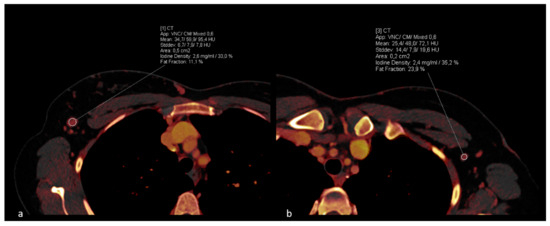

DECT material decomposition values, including iodine density measured in mg/mL and fat fraction represented as a percentage, were extracted, as depicted in Figure 2. To minimize the influence of patient-specific perfusions on the results, additional measurements of the iodine concentration of the thoracic aorta were performed to achieve data normalization for the iodine density.

Figure 2. Case example of a patient with histologically confirmed right-sided breast carcinoma. Pre-operative ROI measurements on Dual-Energy CT iodine maps with identification of metastatic lymph nodes in the right axilla (a). Contralateral measurement demonstrates a healthy lymph node (b).